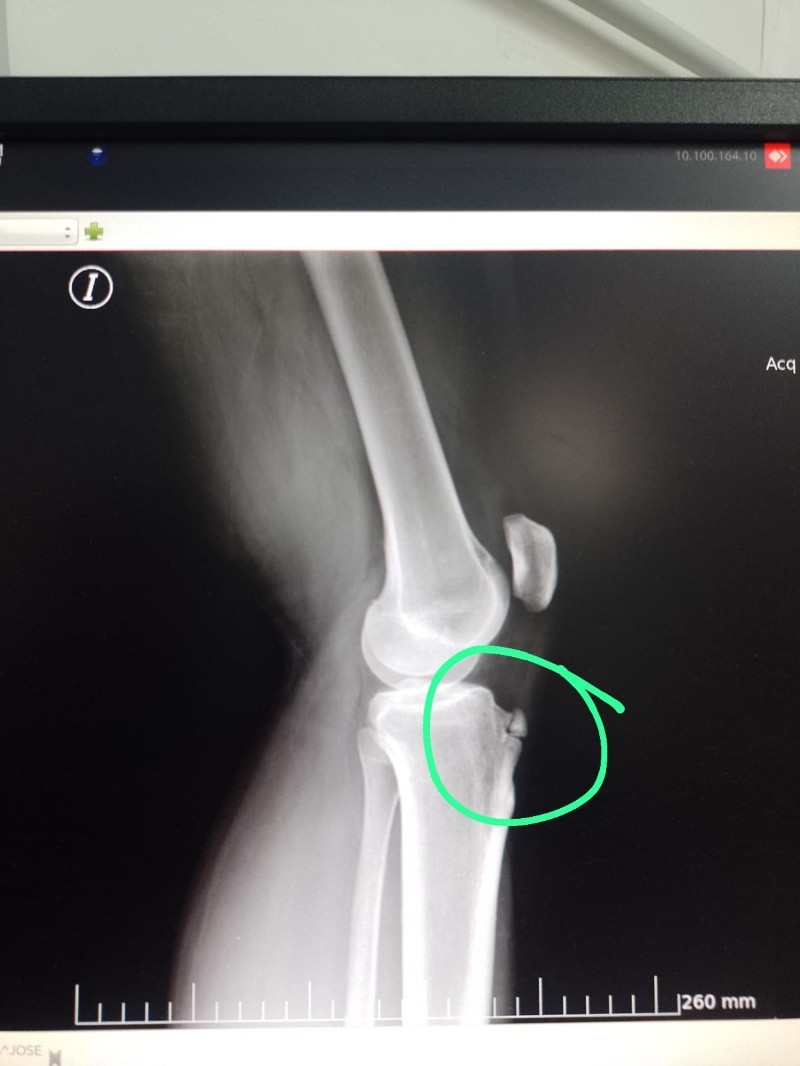

Unos días después, Enrique consiguió turno con la médica clínica del dispensario que, al ver cómo tenía la rodilla y el hombro, lo envió a hacer placas al hospital Centenario. Al día siguiente volvió con los estudios y la mujer le diagnosticó fractura en la rodilla por lo que lo envió a una guardia para que lo atiendan de urgencia.

Ante la desesperación y la falta de respuestas, la esposa de Enrique acudió nuevamente al Cemar y consiguió un turno con otro traumatólogo que le confirmó la fractura pero le explicó que, al haber pasado tanto tiempo, no podía operarlo ni enyesarlo.